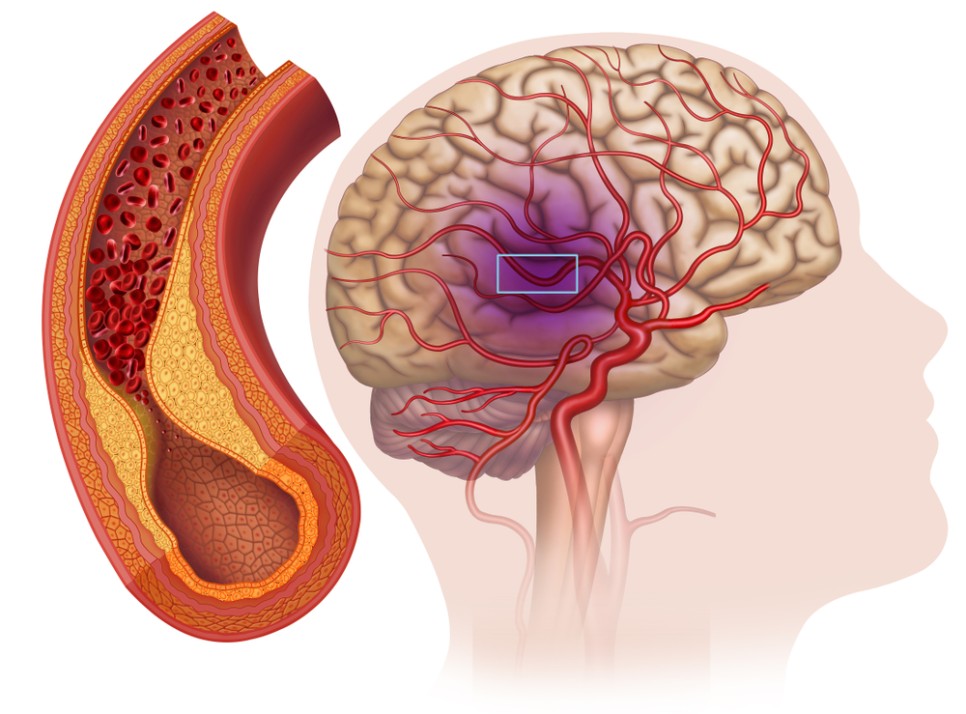

뇌로 가는 혈액의 80%를 보내는 목에 있는 중요한 혈관으로 경동맥의 동맥경화가 진행되면 뇌중풍의 발생 위험이 높아지기 때문입니다. 경동맥에 생긴 찌꺼기가 뇌 혈관으로 흘러 들어가서 뇌 혈관을 막을 확률이 높아집니다.

경동맥이 막히는 질환을 ‘경동맥 협착증’이라고 합니다. 허혈성 뇌중풍(뇌졸중) 원인의 30%를 차지할 정도로 우리 생활에 크게 다가온 경동맥 협착증.

경동맥협착증은 혈관벽 병변에 의해 경동맥이 좁아지는 동맥경화증, 동맥벽이 찢어져 박리되는 경동맥박리증, 대동맥 여러 곳에 발생하는 만성혈관염증은 고야수동맥염 등이 있습니다.

경동맥 협착증의 증상으로는 특별히 초기 증상이 없다는 것이 무서운 점입니다. 혈관이 5060%반 가까이 막혀도 경동맥 협착증이 나타나지 않아 치료시기를 놓치는 경우가 많습니다.

그러나 경동맥이 60% 이상 막히면 현기증, 감각이상, 안면신경마비, 언어장애, 반신부전마비가 나타나게 되고 그때서야 알게 되는 경우가 많습니다.

뇌에 혈관이 막히거나 뇌경색에 의한 뇌기능 마비, 심한 경우 사망할 수도 있습니다.경동맥 협착증 치료